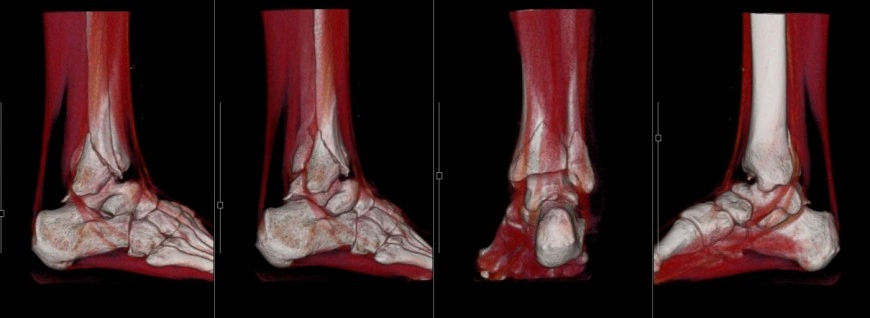

右足関節骨折 3D

右足関節骨折 軟部条件